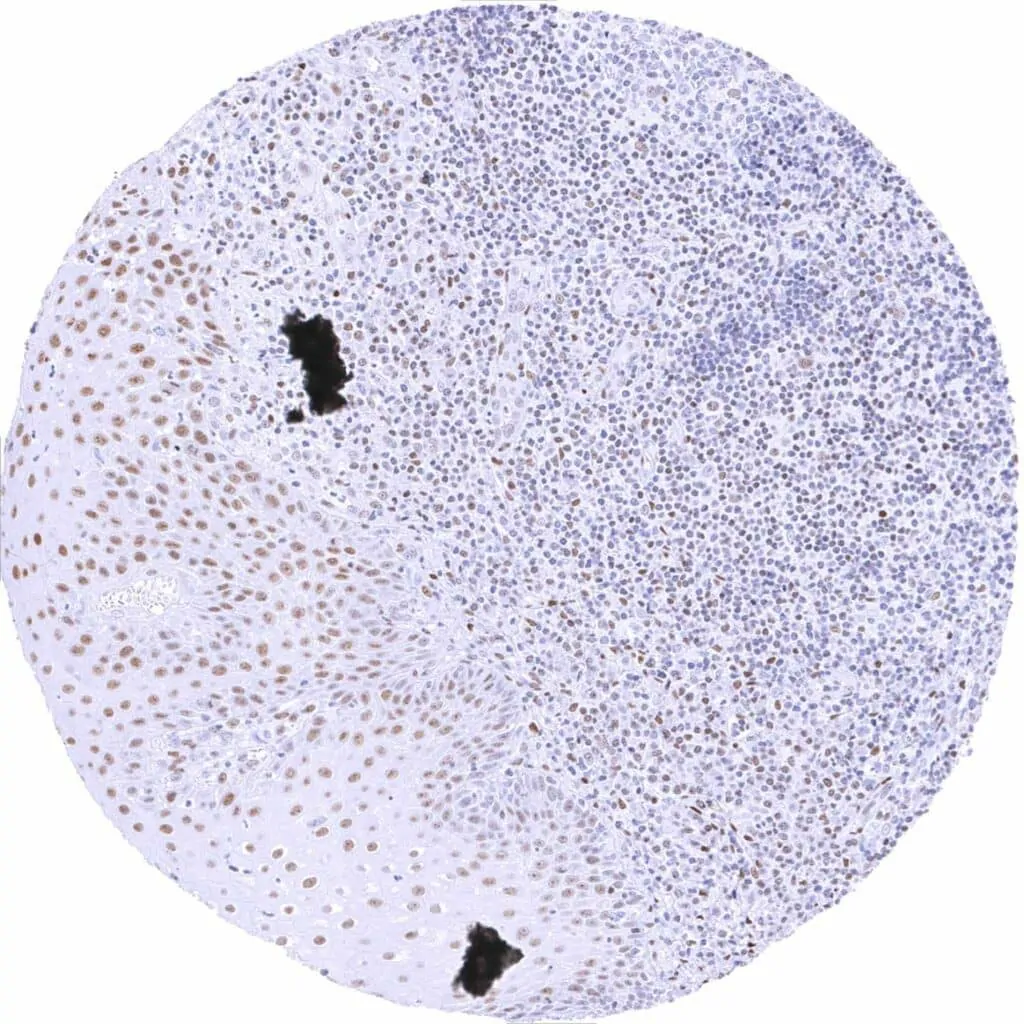

Tonsil – Weak to moderate TLE1 staining in a subset of lymphocytes, predominantly in germinal centres. Moderate TLE1 staining of a major subset of crypt epithelial cells